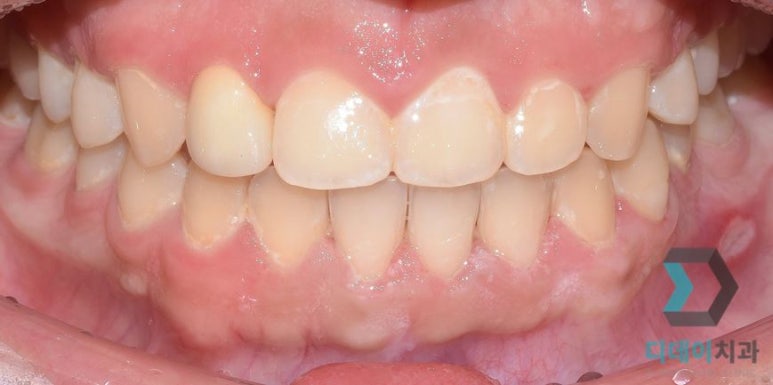

아래 사진과 같이 다양하게 혼합해서 적용할 수도 있고요.

(전) 2021-08-10, (후) 2021-08-19

잇몸성형 + 라미네이트

(전) 2022-06-11, (후) 2022-06-22